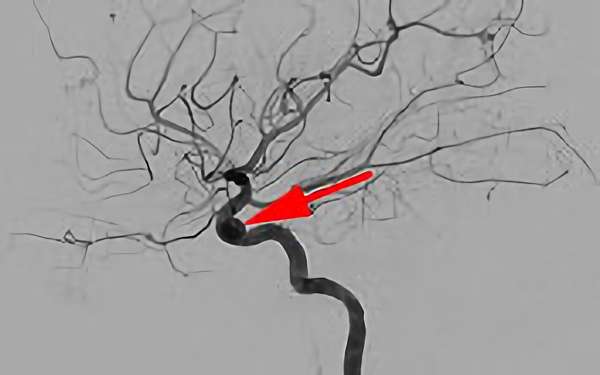

No.1631 手術後